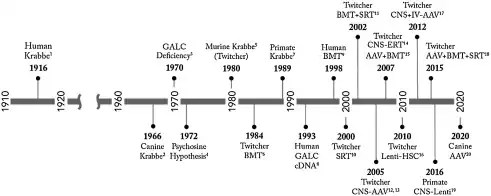

Krabbe disease (KD), also known as globoid cell leukodystrophy[3] and galactosylceramide lipidosis[4], is a rare and often fatal lysosomal storage disease that results in progressive damage to the nervous system. KD involves dysfunctional metabolism of sphingolipids and is inherited in an autosomal recessive pattern. The disease is named after the Danish neurologist Knud Krabbe (1885–1961).[5]

Krabbe disease is caused by mutations in the GALC gene located on chromosome 14 (14q31),[8] which is inherited in an autosomal recessive manner. Mutations in the GALC gene cause a deficiency of an enzyme called galactosylceramidase.[9] In rare cases, it may be caused by a lack of active saposin A (a derivative of prosaposin).[1]

Although there is no known cure for Krabbe disease, bone marrow transplantation or hematopoietic stem cell transplantation (HSCT) has been shown to benefit cases early in the course of the disease. Generally, treatment for the disorder is symptomatic and supportive. Physical therapy may help maintain or increase muscle tone and circulation.

A 15-year study on the developmental outcomes of children with Krabbe disease who underwent HSCT in the first seven weeks after birth found that patients have a better prognosis for both lifespan and functionality, with a slower progression of the disease.[18] Even symptomatic individuals with later-onset Krabbe disease may benefit from HSCT if diagnosed early enough.[19] Umbilical-cord blood is typically used as the source for the transplant stem cells.[20] Clinical trials for gene therapy are currently enrolling patients.[21]

This disease does not only impact humans, but other animals such as monkeys, mice, and dogs have been observed to develop Krabbe disease as well. While certain gene deletions are more frequent than others, novel mutations resulting in Krabbe disease have been discovered worldwide. Most commonly, the underlying cause of the disease is a deletion of a GALC gene, which causes a deficiency in the GALC enzyme. This is the circumstance in 80% of patients who have European and Mexican origins.[22] The mortality rate of early infantile Krabbe disease is 90% before the age of two. Later onset of symptoms is associated with longer life expectancy, with older children generally surviving two to seven years after the initial diagnosis.[23]

Knud Haraldsen Krabbe ( 1885 – 1961) was a Danish neurologist who in 1916, first described what is now known as Krabbe disease.[30]

Animals

Krabbe disease is found in mice[31] may also be found in cats[32] and in dogs, particularly the West Highland White Terriers and Cairn Terriers.[33][34]